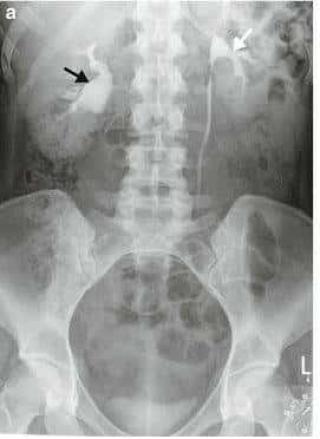

Понимание кавернозного туберкулеза почки